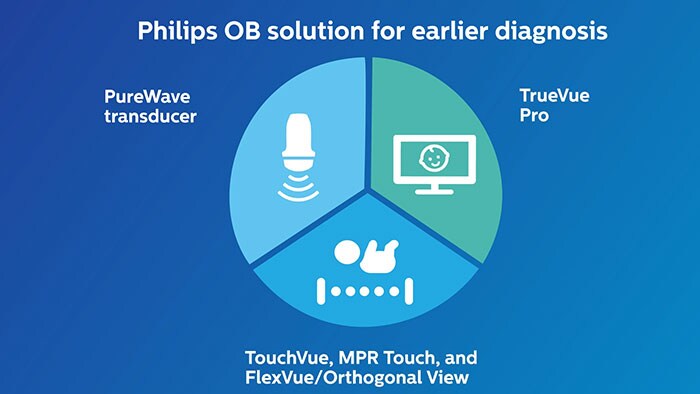

The OB Solution for earlier diagnosis

Philips OB Solution for Earlier Diagnosis VM 6.0